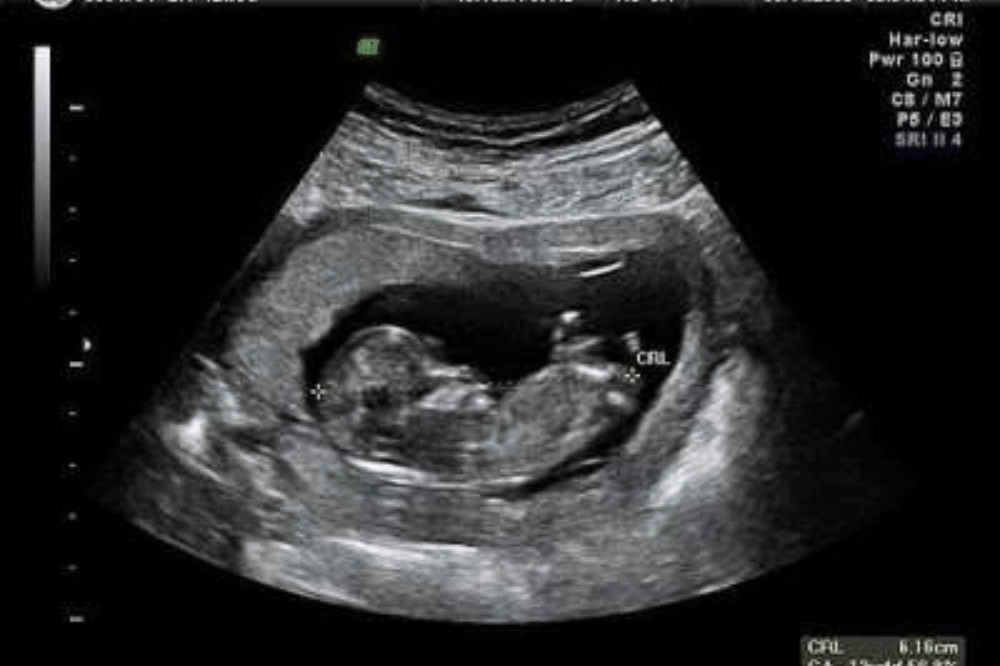

Trimester pertama (sekitar 11–13 minggu)

Secara teknis, penentuan jenis kelamin bayi melalui USG sudah bisa dilakukan sejak minggu ke-11, menggunakan metode seperti genital tubercle angle atau nub theory. Namun, akurasinya masih terbatas. Sebuah penelitian yang dipublikasikan pada PubMed, menunjukkan bahwa tingkat keberhasilan identifikasi saat ada indikasi sudah cukup baik untuk kehamilan 12–13 minggu, yakni mencapai sekitar 94,8% lalu meningkat menjadi hampir 100% pada minggu ke-13.